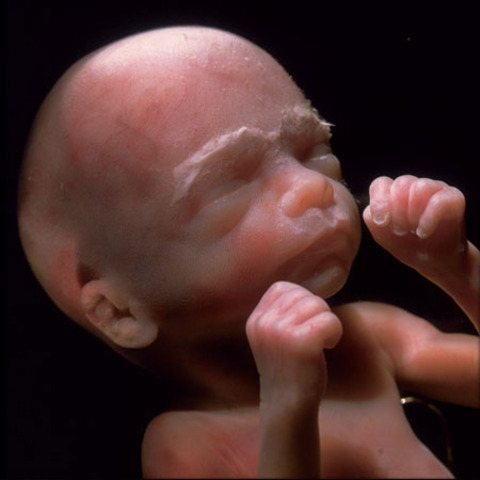

• 9 weeks

9 weeks

The embryonic "tail" is completely gone. Your baby's organs, muscles, and nerves are kicking into gear. The external sex organs are there but won't be distinguishable as male or female for another few weeks. Her eyes are fully formed, but her eyelids are fused shut and won't open until 27 weeks. She has tiny earlobes, and her mouth, nose, and nostrils are more distinct

http://www.babycenter.com/6_your-pregnancy-9-weeks_1098.bc